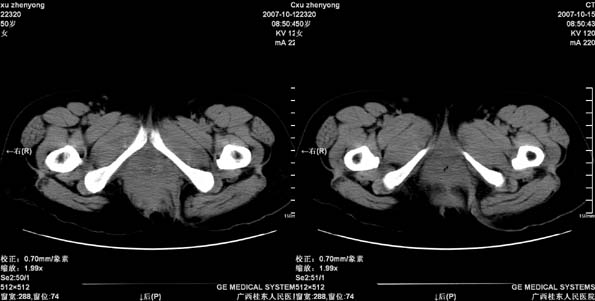

患者,女 50岁.会阴部坠胀感一月余,有痔疮病史,近期有便血;患者今年5月分结肠镜检查未见异常(由于患者不愿意ct增强扫描)没做增强,现准备手术,请各位老师会诊.

直肠壁明显增厚,呈块状表现,肠腔狭窄闭塞,考虑ca

直肠壁增厚明显,周围脂肪间隙模糊,见有小淋巴结显示,前方与阴道后壁分解不清。考虑直肠癌可能性大

不做强化,但平扫保留灌肠一定要做好。现在看直肠壁增厚明显,周围脂肪间隙模糊,前方与阴道后壁分界不清。考虑直肠癌可能性大

直肠下端及肛门周围可见软组织改变,如果5月份检查的结肠镜结果可靠,那么本病例痔的可能性还是很大的。肿瘤生长的不会如此之快。

这个患者做了手术,术中直肠及会阴部均求见肿瘤,探查要中未作特殊处理.患者准备复查,我会急时上传图象